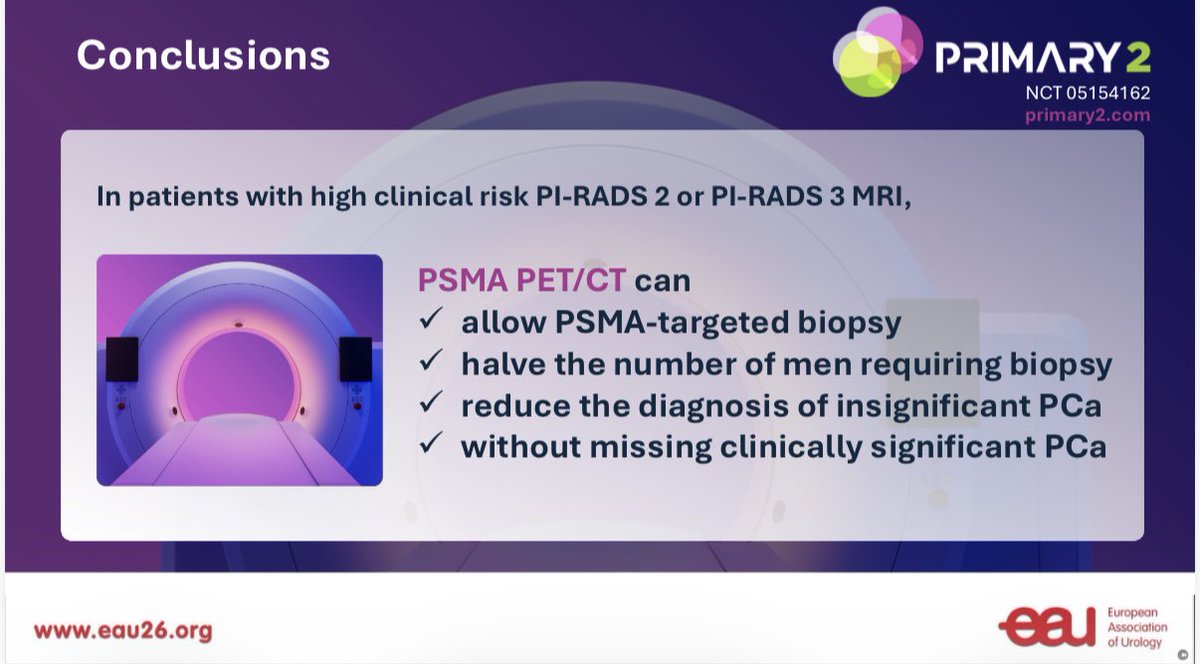

🚨 Gamechanger #PRIMARY2 RCT #EAU26, presented and in press The Lancet Oncology. PSMA-PET CT in men with equivocal or -ve MRI but red flags results reduces biopsy by 49% and has non-inferior csPCa detection to template biopsy in all. Proud to be part of this🚨